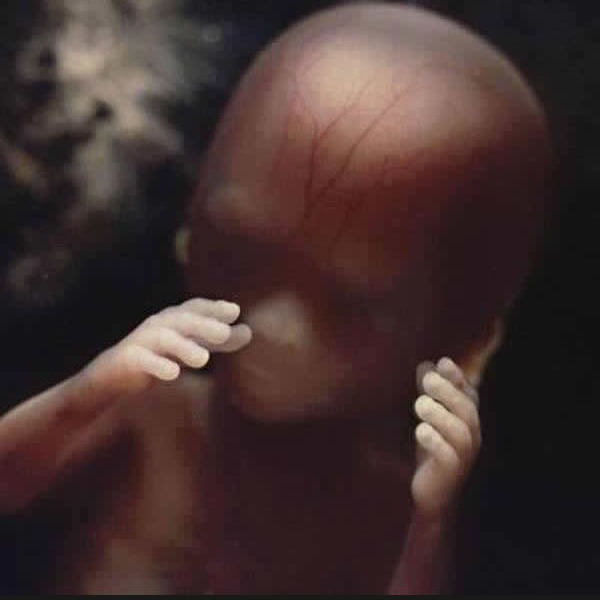

8. hét